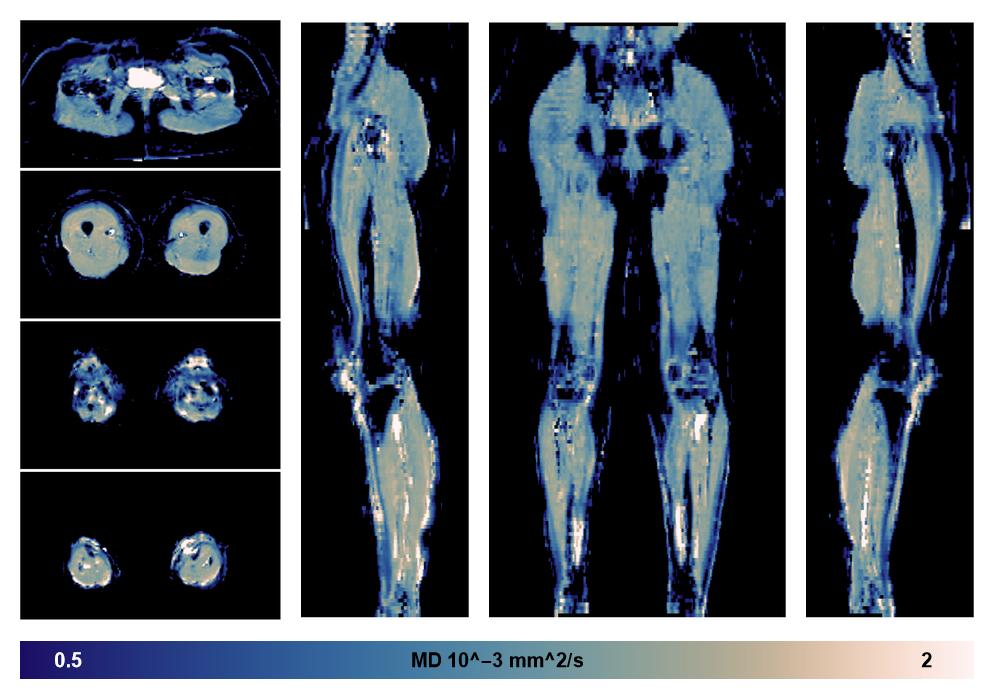

• Mean diffusivity

IVIM corrected whole leg muscle mean diffusivity obtained from diffusion tensor imaging.